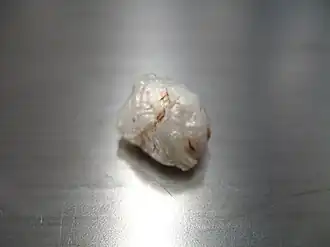

Macroscopic appearance of a resected (surgically removed) intracranial cyst, with pearl appearance

Macroscopic appearance of a resected (surgically removed) intracranial cyst, with pearl appearance -